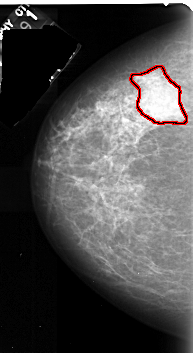

FILE: A_1036_1.LEFT_CC.OVERLAY

TOTAL_ABNORMALITIES 1

ABNORMALITY 1

LESION_TYPE MASS SHAPE IRREGULAR MARGINS ILL_DEFINED

ASSESSMENT 4

SUBTLETY 5

PATHOLOGY MALIGNANT

TOTAL_OUTLINES 1

BOUNDARY